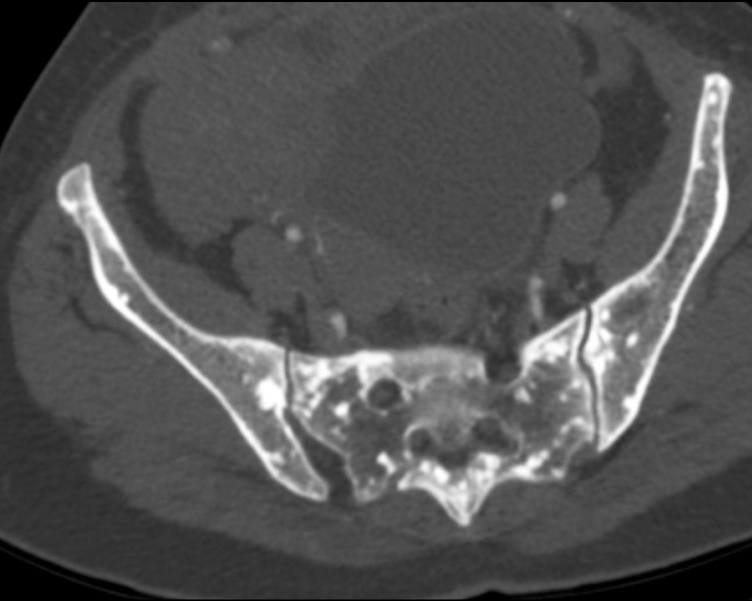

Osteopoikilosis is a rare inherited benign bone dysplasia incidentally found on radiological exams. It is characterized by a specific radiological pattern: diffuse, round or oval, symmetrically shaped sclerotic bone areas distributed throughout the skeleton. It is essential to do a correct diagnosis because these lesions could be easily confused with bone metastasis.

We reported a case of an osteopoikilosis patient presenting to our clinic with transient loss of consciousness and without any numbness, tingling and weakness in the legs or other parts of the body. The computed tomography scan showed multiple small sclerotic foci bone islands, scattered throughout the thoracic and lumbar spine, ribs, pelvic bone, sacrum and bilateral proximal femur. No significant increase in the activity was detected in technetium-99m whole-body bone scintigraphy. The patient was diagnosed with characteristic radiological findings of osteopoikilosis and was followed up.